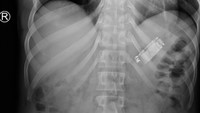

Tim dokter terkejut saat hasil CT-scan menunjukkan bentuk ponsel utuh di dalam lambung pasien. Kasus langka ini langsung menarik perhatian tim bedah dan radiologi. (Foto: Cureus Journal)